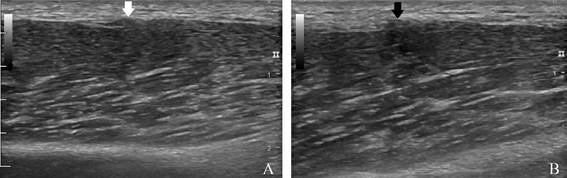

A ultrassonografia detectou falha da fáscia muscular do extensor longo dos dedos na região referida medindo cerca de 0,3 cm, com herniação muscular em cerca de 0,4 x 0,2 cm (Figura 2).

Figura 2: Ultrassonografia da perna esquerda demonstrando falha da fáscia muscular com herniação do músculo extensor longo dos dedos com sua contração em A (seta branca) e demonstrando em B, com o músculo relaxado, a herniação muscular menos evidente (seta preta).

O exame físico destes pacientes pode revelar se há presença de sinal de Tinel positivo na região do referida. (1,2 O ultrassonografista, sem exercer pressão significativa com o transdutor, pode escanear dinamicamente para determinar a presença de um defeito fascial durante a contração muscular e manipulação posicional. (1 A ultrassonografia é vantajosa, pois é realizada em tempo real, sendo a hérnia muscular detectada durante o exame dinâmico e a natureza da lesão pode ser demonstrada ao paciente, o que ajuda em sua segurança no diagnóstico e posterior tratamento. (1

Tanto a ultrassonografia quanto a ressonância magnética (RM) podem demonstrar interrupção da fáscia profunda com herniação de um componente muscular periférico em continuidade com o restante das fibras musculares, mostrando a mesma ecogenicidade ou intensidade de sinal do próprio músculo. (1 Esses recursos podem ajudar a diferenciar as hérnias musculares de outras lesões, tais como hematomas, cistos epidermóides, malformações arteriovenosas, schwannomas, roturas musculares e lipomas. (1

O ultrassonografista deve estar atento à possibilidade da hérnia muscular, reduzindo os riscos de complicações e diagnósticos equivocados. (3 Existe a vantagem da avaliação dinâmica da ultrassonografia sobre os demais exames, possibilitando a averiguação da herniação com a contração e repouso muscular. A ultrassonografia apresenta ótimo custo-benefício devido a sua boa sensibilidade, acessibilidade e custo, reduzindo gastos maiores com exames mais complexos, tais como a ressonância magnética, para exclusão de outras doenças. (3